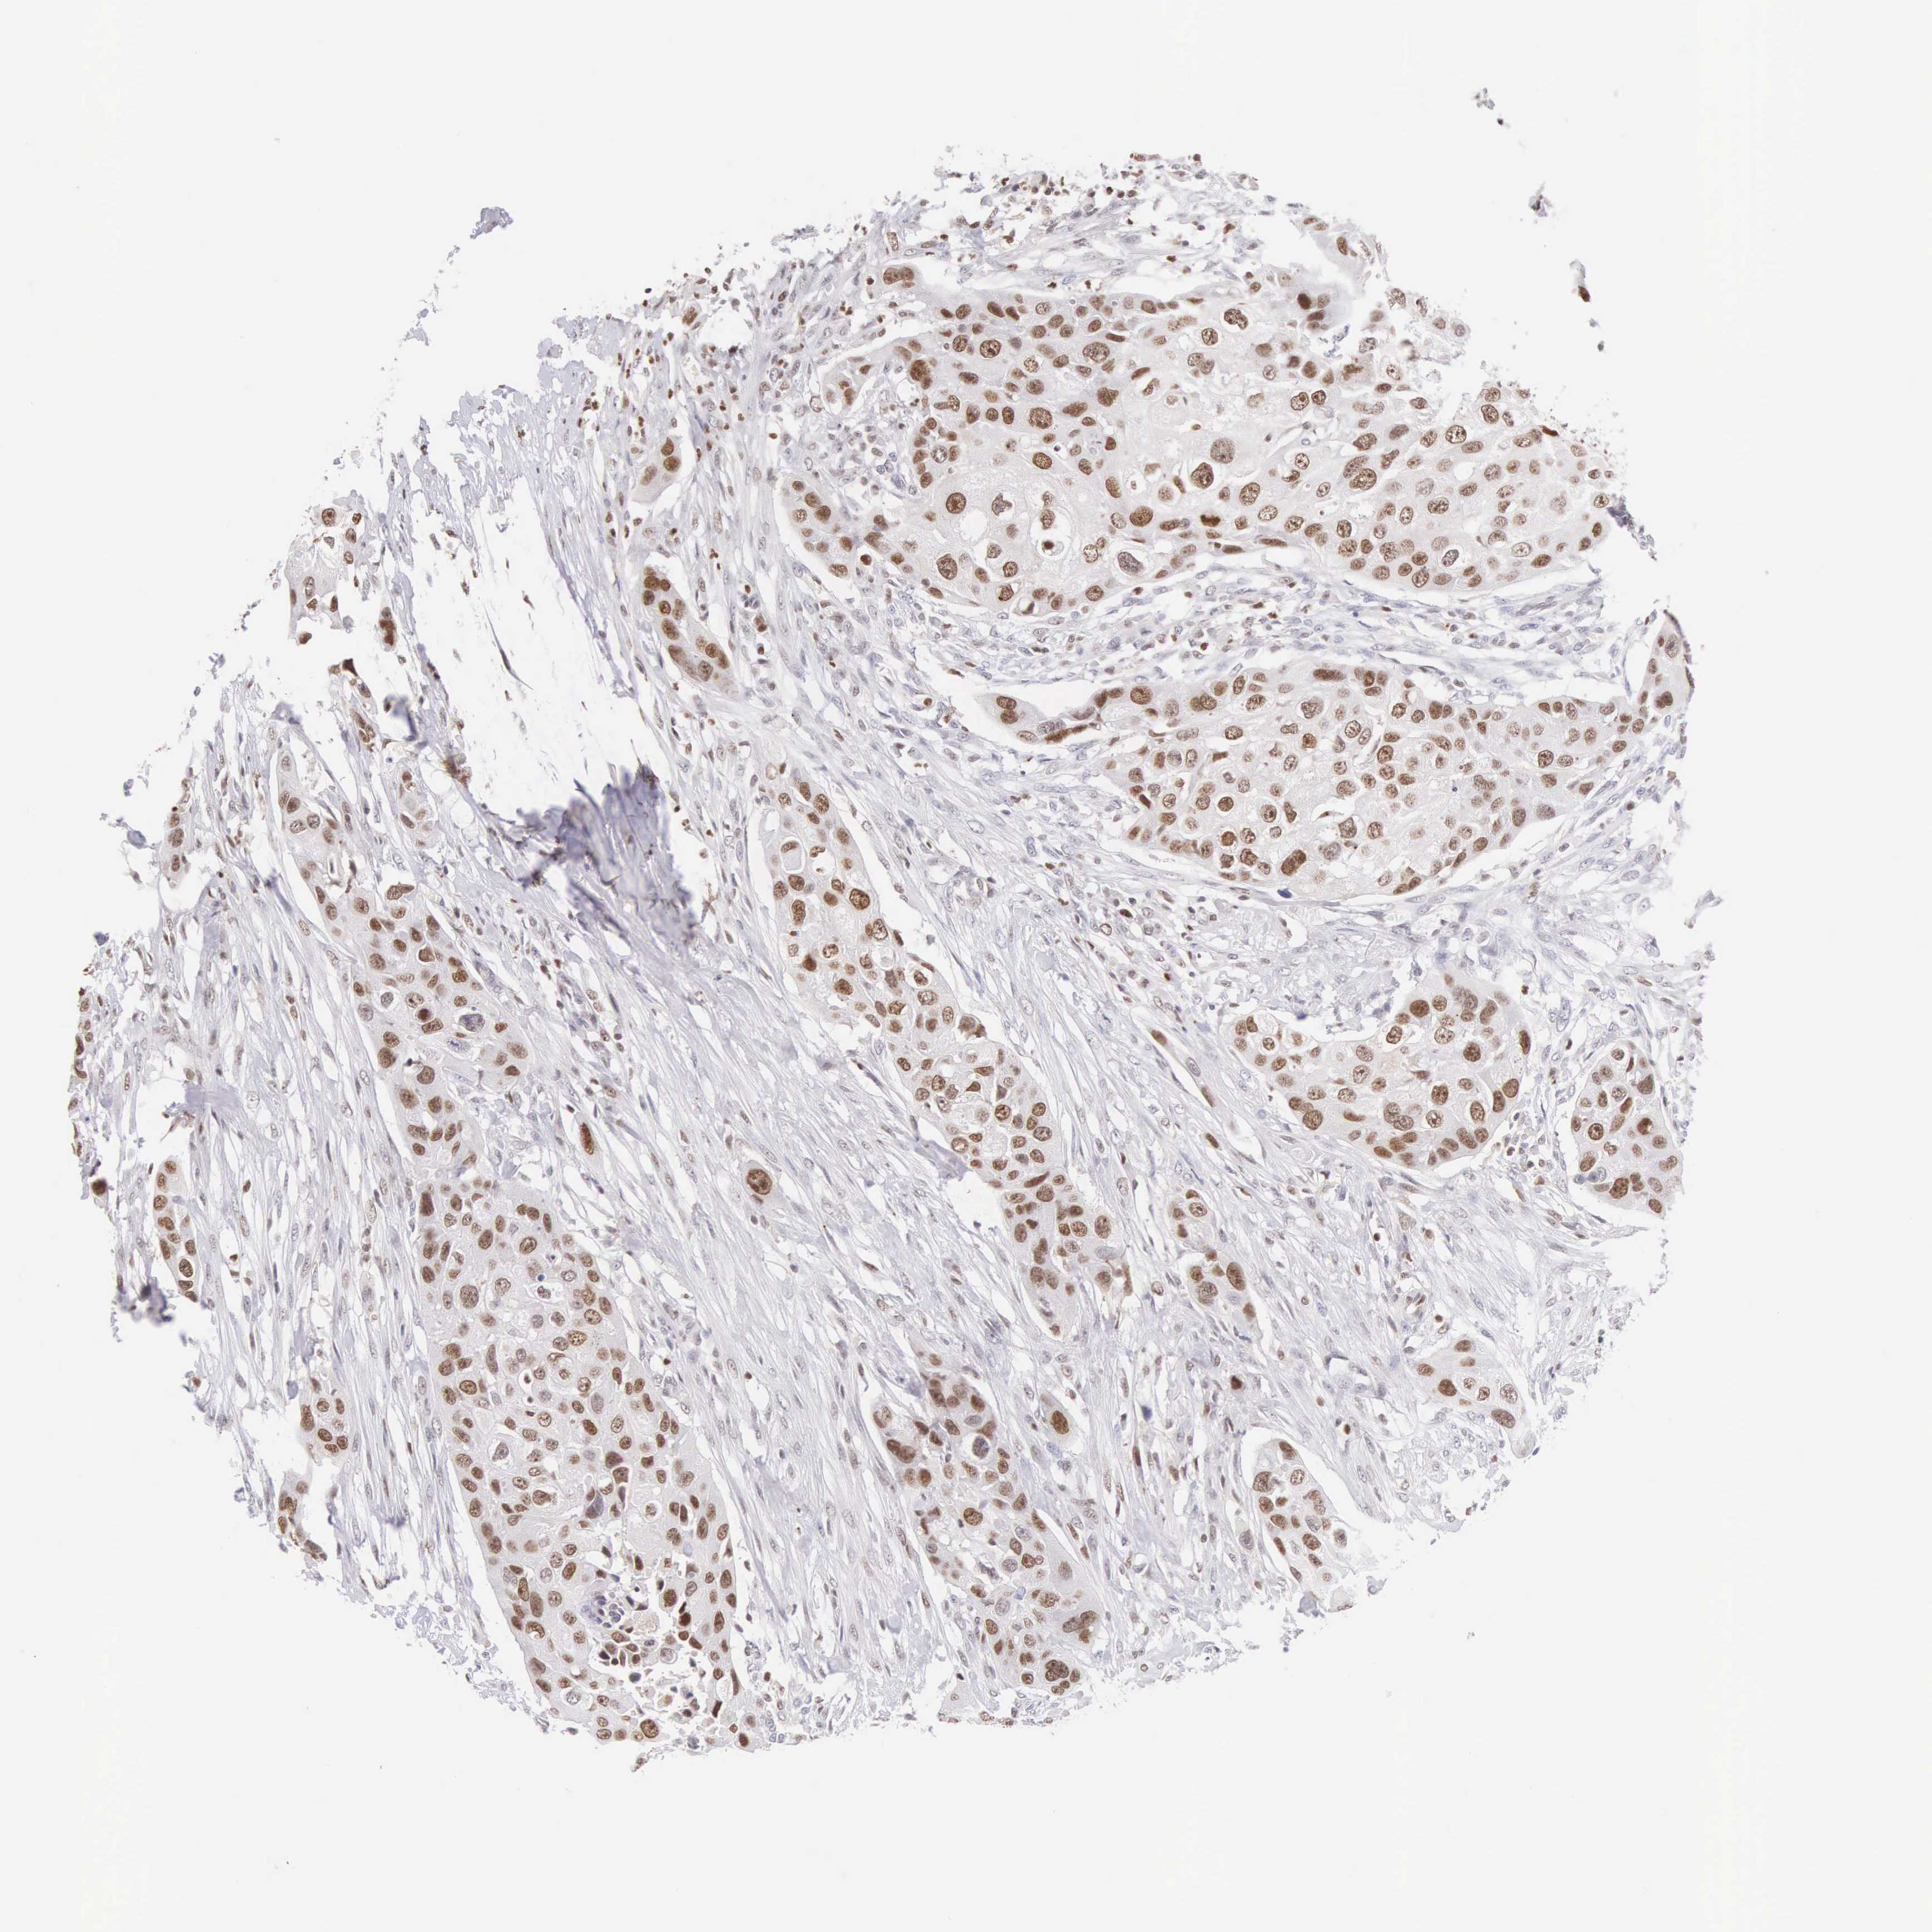

UROTHELIAL CANCER - Protein expressioni

A mouse-over function shows sample information and annotation data. Click on an image to view it in a full screen mode. Samples can be filtered based on level of antibody staining by selecting one or several of the following categories: high, medium, low and not detected. The assay and annotation is described here.

Antibody stainingi

Antibody staining in the annotated cell types in the current human tissue is reported as not detected, low, medium, or high, based on conventional immunohistochemistry profiling in selected tissues. This score is based on the combination of the staining intensity and fraction of stained cells.

Each image is clickable and will lead to virtual microscopy that enables deeper exploration of all samples and also displays staining intensity scores, fraction scores and subcellular localization as well as patient and tissue information for each sample.

Antibody HPA017929

Urothelial carcinoma, Low grade